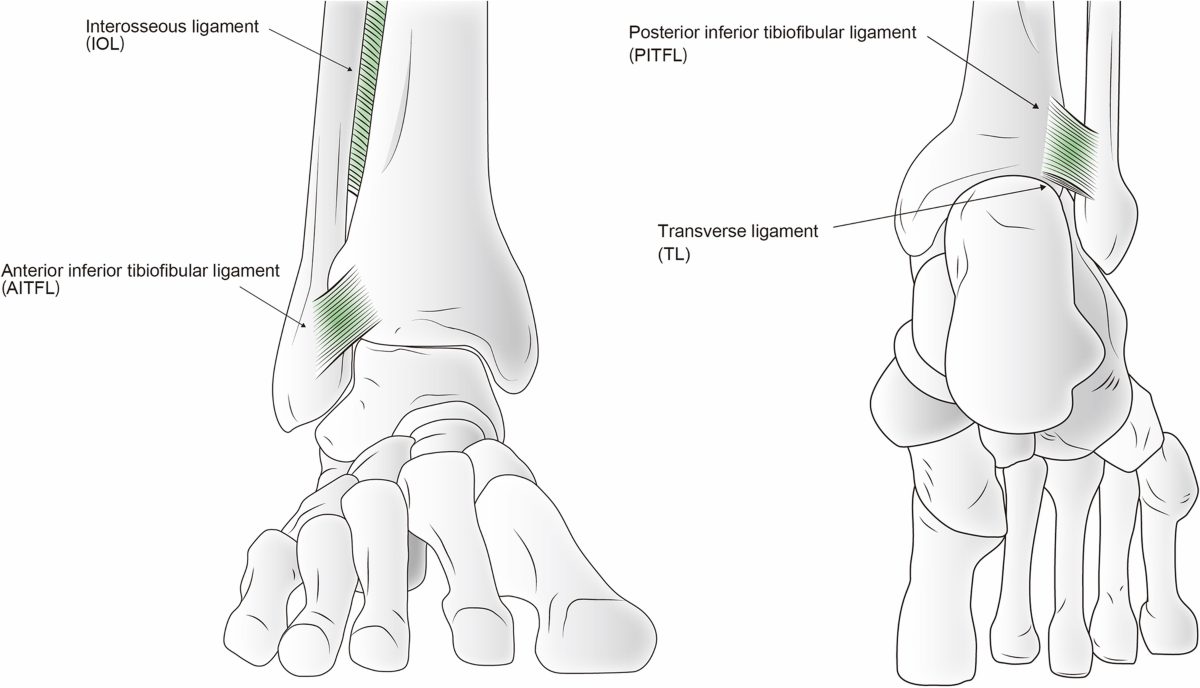

Связочный аппарат синдесмоза

Рис. 5. Анатомия межберцового синдесмоза. Показаны четыре основные связки: передняя нижняя большеберцово-малоберцовая связка (AITFL), задняя нижняя большеберцово-малоберцовая связка (PITFL), межкостная мембрана (interosseous membrane) и поперечная связка (transverse ligament). Адаптировано из Liu et al., 2022, CC BY-NC 3.0.

Четыре связки формируют синдесмотический связочный комплекс: передняя нижняя большеберцово-малоберцовая связка (ПНБМс, AITFL), задняя нижняя большеберцово-малоберцовая связка (ЗНБМС, PITFL), большеберцово-малоберцовая межкостная связка (БММС, TFIL) и поперечная межберцовая связка (TTFL). Эти связки совместно с костными структурами обеспечивают целостность соединения между дистальными отделами большеберцовой и малоберцовой костей, противодействуя осевым, ротационным и трансляционным нагрузкам.

передняя нижняя большеберцово-малоберцовая связка (ПНБМс, AITFL)

ПНБМс проходит косо от переднего бугорка дистальной части большеберцовой кости (фрагмент Тиллау-Шапут), в среднем на 5 мм проксимальнее суставной поверхности, к переднему бугорку дистальной части малоберцовой кости. Связка имеет мультифасцикулярное строение — между пучками коллагеновых волокон расположена жировая ткань.

ПНБМс разделена на три части. Верхняя — самая короткая, начинается чуть проксимальнее переднего бугорка большеберцовой кости и прикрепляется чуть проксимальнее переднего бугорка малоберцовой кости. Средняя — наиболее прочная, проходит между передними бугорками большеберцовой и малоберцовой костей. Нижняя часть — самая длинная, распространяется дистальнее передних бугорков.

Добавочная передняя нижняя большеберцово-малоберцовая связка, известная как связка Бассетта (Bassett’s ligament), определяется в 21–92% случаев при анатомических препарациях и МРТ-исследованиях. Она проходит дистальнее и параллельно ПНБМс, не покрыта синовиальной тканью, является внутрисуставной структурой, пересекает проксимально-латеральный край голеностопного сустава и при тыльном сгибании контактирует с латеральным блоком таранной кости. Именно связка Бассетта может быть причиной переднелатерального импинджмента.

ПНБМс — самая слабая из четырёх синдесмотических связок и первой поддаётся нагрузкам, вызывающим наружную ротацию малоберцовой кости вокруг её продольной оси.

задняя нижняя большеберцово-малоберцовая связка (ЗНБМС, PITFL)

ЗНБМС — мощная связка, идущая от задней лодыжки большеберцовой кости к заднему бугорку малоберцовой кости в направлении от проксимально-медиального к дистально-латеральному. По форме и структуре она аналогична ПНБМс — мультифасцикулярна, состоит из множественных пучков коллагена с прослойками жировой ткани. Её нижняя часть, или поперечная связка (TTFL), расположена более горизонтально.

Поскольку ЗНБМС — толстая и прочная связка, чрезмерные нагрузки чаще приводят не к её разрыву, а к отрывному перелому задней лодыжки (фрагмент Фолькманна, Volkmann).

Поперечная межберцовая связка (TTFL)

Поперечная связка проходит горизонтально между проксимальным краем лодыжковой ямки малоберцовой кости и задненижним краем большеберцовой кости, иногда достигая задней поверхности внутренней лодыжки. Это толстая округлая связка, которая углубляет задненижний край большеберцовой кости и формирует аналог суставной губы (labrum analogue). Часть волокон задней таранно-малоберцовой связки (PTFL) сливаются с наиболее дистальными волокнами поперечной связки, образуя так называемый tibial slip, или межлодыжковую связку (IML).